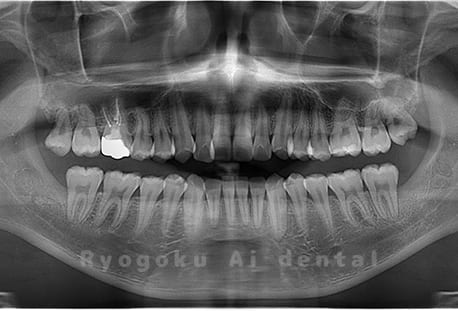

Case01

- 原因

- 水平埋伏智歯

- 治療内容

- 下顎の水平埋伏智歯を抜歯

<リスク・副作用>

手術後は痛み、腫れ、痺れなどの副作用が生じる場合があります。